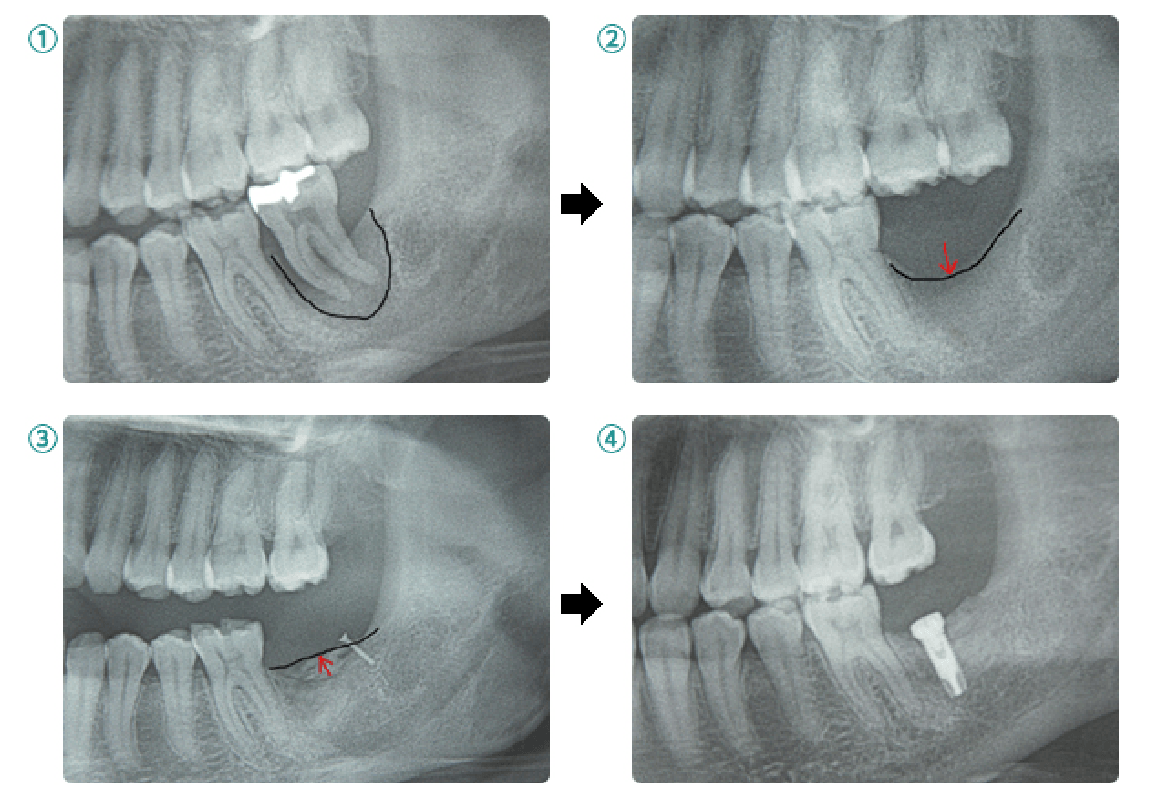

骨造成術

インプラントを埋入するだけの骨がない場合に異種他家骨※1や自家骨※2を移植しインプラントを埋入できるようにします。インプラント埋入と同時に行う場合と、インプラント埋入前に行う場合があります。

※1 異種他家骨は牛骨由来移植材(Bio-Ossやボーンジェクト)を使用しています。狂牛病やヤコブ病など異常プリオン由来の感染の危険性について安全性に問題ないとされており、厚生労働省の承認を得ています。ソケットリフト、サイナスリフトで多く使用します。

※2 自家骨は患者様本人の骨を意味します。当院では下顎臼歯部後方や下顎隆起、口蓋隆起部などから採取しています。インプラント手術部位以外にも手術部位が増えてしまうという欠点がありますが、未知の疾病の感染がないという面において、安全性が高い上、骨誘導能にも優れている利点があります。また、アゴの欠損が大きい方にべニア(オンレー)グラフトができる利点があります。

べニア(オンレー)グラフト

自家骨を用いた骨造成術の一つで、ブロック状あるいは板状に採取した骨をインプラント部位に移植して、チタン製スクリューで固定する方法。

ソケットリフトとサイナスリフト

上顎臼歯部には上顎洞(副鼻腔の一つ)が存在し、骨の高さが足りない場合があります。その場合、上顎洞底部の洞粘膜(シュナイダー膜)を挙上し、挙上によってできた空隙に骨移植を行い骨造成し、インプラントが埋入できるようにします。当院では骨の高さが5~6mm以上の場合にソケットリフト、5~6mm未満の場合にサイナスリフトを行います。つまり、たくさんの骨移植が必要な場合にはサイナスリフトになります。